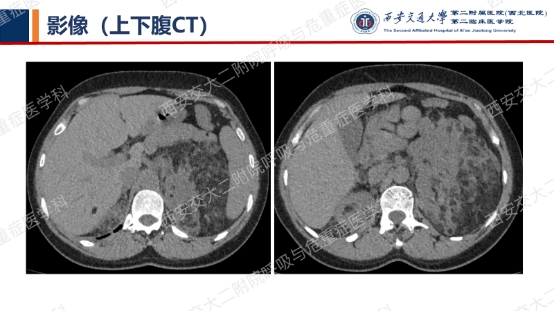

患者无吸烟史,二手烟接触不多。追问家族史,父母已故(具体不详),兄弟姐妹6人,大姐有肺大泡病史,未具体诊治,育有2子,均体健。进一步行双肾CT平扫提示双肾轻度积水,进一步行全外显子基因检测,回报FLCN突变:

该例患者BHD诊断明确,无皮肤及肾脏受累,仅表现为多发囊性肺病变。建议忌烟,避免受凉、劳累及剧烈运动,防范气胸。鉴于肺功异常,建议每年复查1次胸部CT及肺功能检查;每3年筛查1次肾脏MRI。同时建议其兄弟姐妹及其子完善症状前FLCN基因检测。